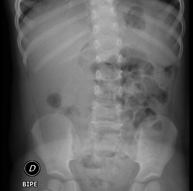

- RX Abdomen

Tècnica que usa els raigs X a través de la qual s'obtenen imatges de l'abdomen (estómac, intestí prim, intestí gros, fetge, ronyons, bufeta, pelvis òssia, etc.) per al seu estudi. - RX Columna lumbar

Una radiografia de tòrax és una tècnica mitjançant la qual, amb l'ús d'una petita dosi de radiació, s'obté una imatge bidimensional de la caixa toràcica i el seu contingut (pulmons, cor, mediastí, etc. ). És una de les proves mèdiques realitzades més comuna. - RX Abdomen

Una radiografia d'abdomen és una tècnica mitjançant la qual, amb l'ús d'una petita dosi de radiació, s'obté una imatge bidimensional de l'abdomen amb les seves estructures anatòmiques (estómac, intestí prim, intestí gros, fetge, pàncrees, ronyons, bufeta, pelvis òssia, etc.) - Telerradiologia columna